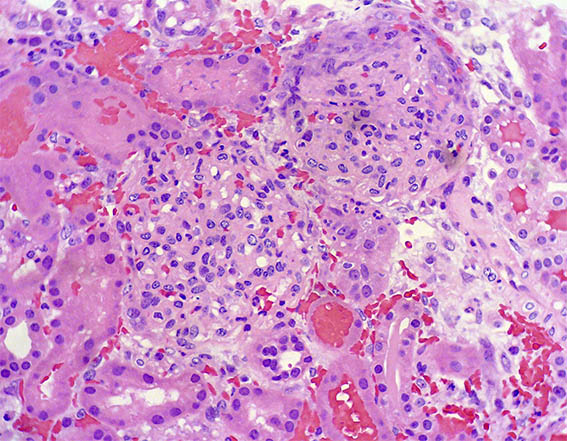

Figure 3. H&E, X200.

Figure 4. H&E, X200.